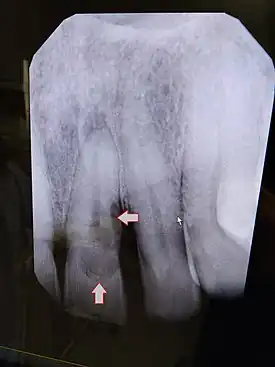

![]() | |

| Post traumatic External tooth resorption 9 | |

External inflammatory root resorption may be caused by trauma to the root surface, due to damage to the periodontal ligament (PDL) and/or extended drying following tooth avulsion. Following trauma, dentinal tubules are exposed leading to communication with an infective or necrotic pulp. This leads to an inflammatory process that causes external root resorption.[16]